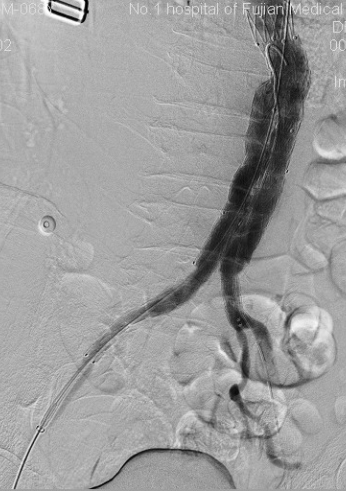

腹主动脉瘤